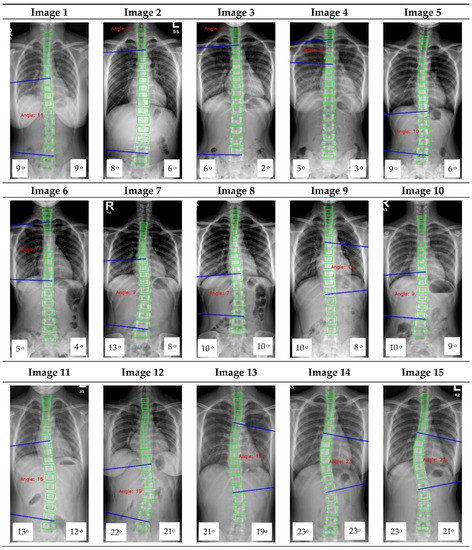

The Cobb angle (CA) serves as the principal method for assessing spinal deformity, but manual measurements of the CA are time-consuming and susceptible to inter- and intra-observer variability. While learning-based methods, such as SpineHRNet+, have demonstrated potential in automating CA measurement, their accuracy can be influenced by the severity of spinal deformity, image quality, relative position of rib and vertebrae, etc. Our aim is to create a reliable learning-based approach that provides consistent and highly accurate measurements of the CA from posteroanterior (PA) X-rays, surpassing the state-of-the-art method. To accomplish this, we introduce SpineHRformer, which identifies anatomical landmarks, including the vertices of endplates from the 7th cervical vertebra (C7) to the 5th lumbar vertebra (L5) and the end vertebrae with different output heads, enabling the calculation of CAs. Within our SpineHRformer, a backbone HRNet first extracts multi-scale features from the input X-ray, while transformer blocks extract local and global features from the HRNet outputs. Subsequently, an output head to generate heatmaps of the endplate landmarks or end vertebra landmarks facilitates the computation of CAs. We used a dataset of 1934 PA X-rays with diverse degrees of spinal deformity and image quality, following an 8:2 ratio to train and test the model. The experimental results indicate that SpineHRformer outperforms SpineHRNet+ in landmark detection (Mean Euclidean Distance: 2.47 pixels vs. 2.74 pixels), CA prediction (Pearson correlation coefficient: 0.86 vs. 0.83), and severity grading (sensitivity: normal-mild; 0.93 vs. 0.74, moderate; 0.74 vs. 0.77, severe; 0.74 vs. 0.7). Our approach demonstrates greater robustness and accuracy compared to SpineHRNet+, offering substantial potential for improving the efficiency and reliability of CA measurements in clinical settings. Full article

Figure 1